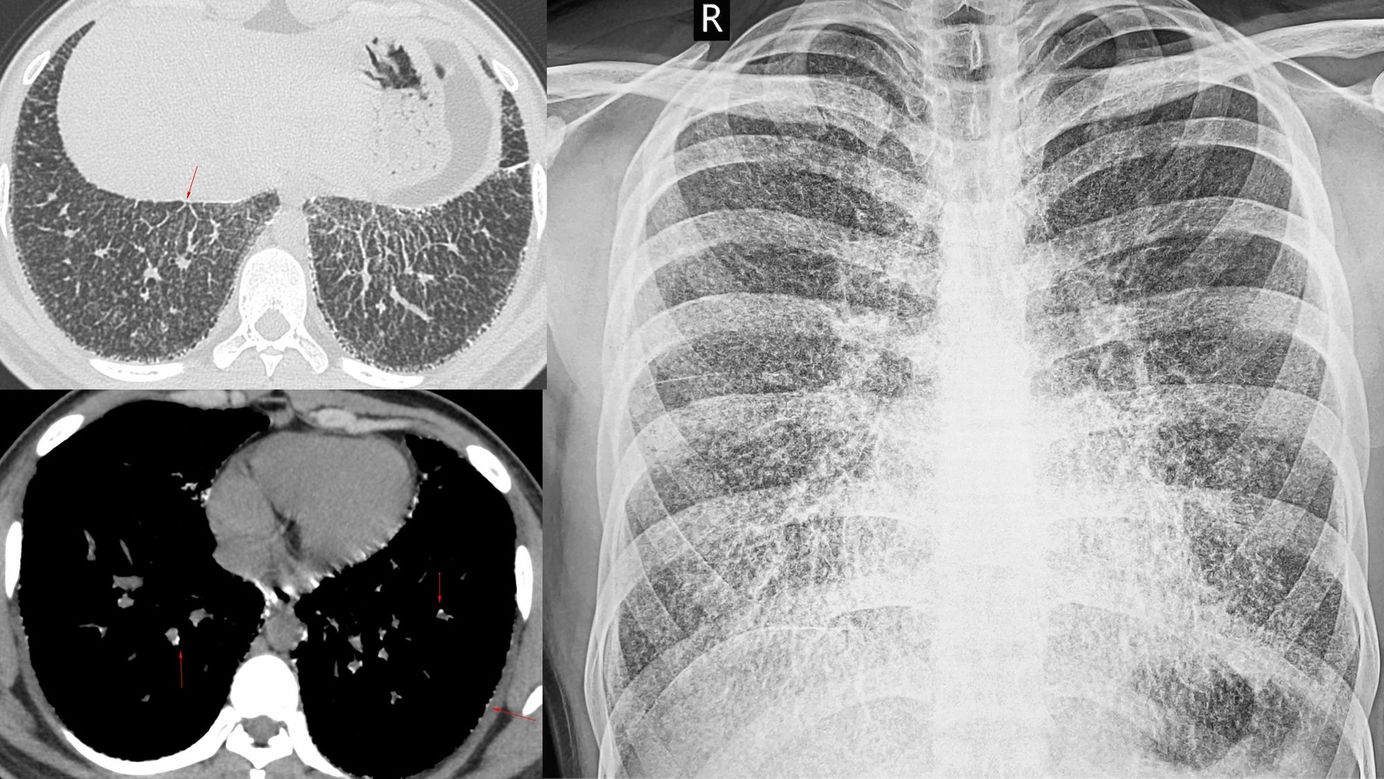

Case 4: Lymphangitis Carcinomatosis Members Public

70-years old lady with Ca breast, with progressive dyspnea. She had nodular septal thickening in the right lung, more in the right lower lobe with larger discrete nodules. These findings are characteristic of lymphangitis carcinomatosis